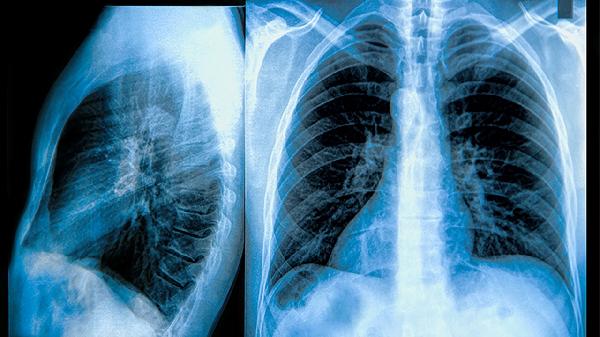

做胸部CT能检查出什么

胸部CT能检出肺部感染、肺结节、胸腔积液、纵隔肿瘤及心血管异常等多种病变。1、肺部感染胸部CT对细菌性肺炎、病毒性肺炎等感染性病变敏感度高,可显示斑片状或磨玻璃......

ct检查肺部有炎症治疗方法有哪些

肺部炎症可通过抗感染药物治疗、糖皮质激素治疗、祛痰治疗、氧疗及生活干预等方式改善,通常由细菌感染、病毒感染、真菌感染、理化因素刺激或自身免疫性疾病等因素引起。建......